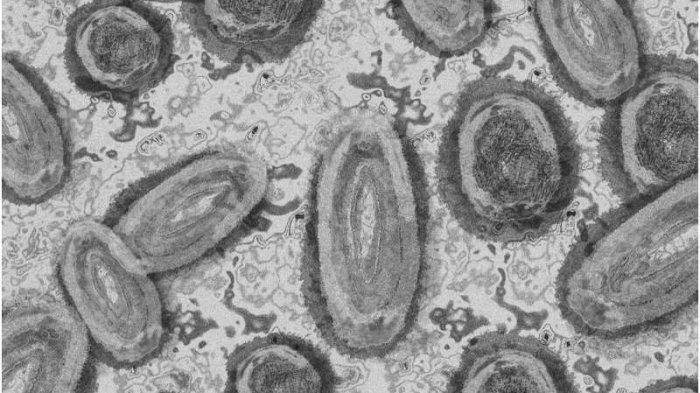

Cacar monyet sendiri adalah virus DNA besar milik keluarga orthopoxvirus.

Orthopoxvirus adalah virus stabil yang tidak banyak bermutasi.

Namun, virus penyebab wabah saat ini memiliki beberapa mutasi dibandingkan dengan versi virus yang beredar di Afrika.